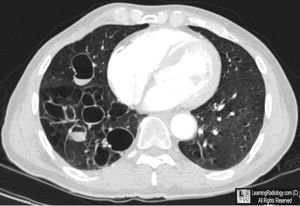

What's your diagnosis?

1.bronchectasis 2.emphysema 3.pneumothorax 4.pleural effusion

No.it has signet ring.it's bronchectasis

No.look to signet ring

No.look at signet rings.it's bronchectasis

Look at signet rings...!

It looks more like bronchiectasis.